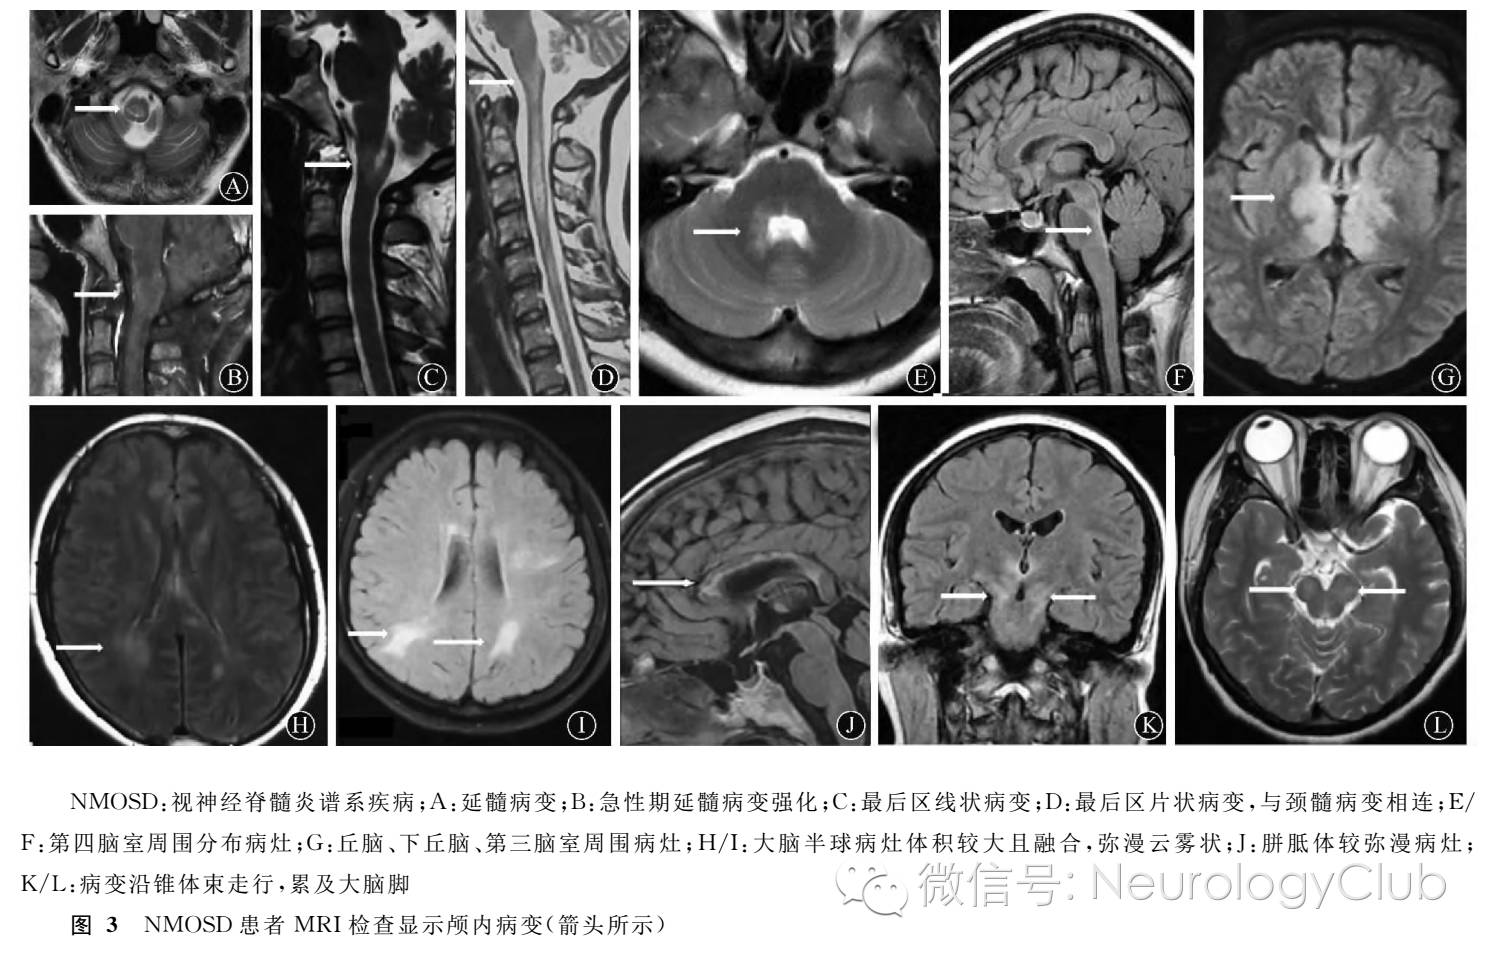

2.1 NMOSD的临床表现与MRI影像特征  NMOSD有6组核心临床症候,其中ON、急性脊髓炎、延髓最后区综合征的临床及影像表现最具特征性。需要强调的是每组核心临床症候与影像同时对应存在时支持NMOSD的诊断特异性最高,如仅单一存在典型临床表现或影像特征,其作为支持诊断的特异性会有所下降(ON的MRI特征可以为阴性,后三组临床症候可以为阴性)。结果见表1、 图1-3。

传统概念的NMO被认为病变仅局限于视神经和脊髓。随着深入研究发现,NMO的临床特征更为广泛,包括一些非视神经和脊髓表现。这些病变多分布于室管 膜周围AQP4高表达区域,如延髓最后区、丘脑、下丘脑、第三和第四脑室周围、脑室旁、胼胝体、大脑半球白质等。AQP4-IgG的高度特异性进一步扩展了对NMO及其相关疾病的研究。临床上有一组尚不能满足NMO诊断标准的局限形式的脱髓鞘疾病,可伴随或不伴随AQP4-IgG阳性,例如单发或复发性ON(ON/r-ON) 、单发或复发性LETM(LETM/r-LETM)、伴有风湿免疫疾病或风湿免疫相关自身免疫抗体阳性的ON或LETM等,它们具有与NMO相似的发病机制及临床特征,部分病例最终演变为NMO。2007年Wingerchuk等把上述疾病统一命名为视神经脊髓炎谱系疾病(neuromyelitis optica spectrum disorders,NMOSD)

2.2.5 其他脑病类型:部分病例在疾病的某一阶段可以单独或合并出现与NMOSD脑内特征影像对应的临床症候。(1)脑干及第四脑室周边症候:头晕、复视、共济失调等;(2)下丘脑症候:困倦、发作性睡病样表现、顽固性低钠血症、体温调节障碍等;(3)大脑半球白质或胼胝体症候:淡漠、反应迟缓、认知水平下降、头痛等;(4)可无任何症候